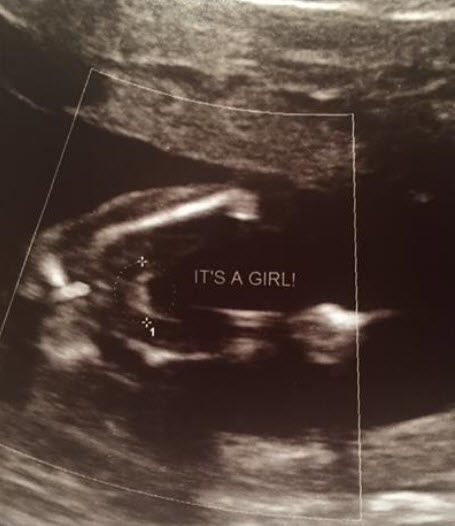

Had an elective U/S at 16 weeks, 4 days. Tech was 150% sure our little princess is indeed, a princess! We are over the moon excited, and so is Big Brother!

:DS: April 2015 | :DD: EDD December 2017